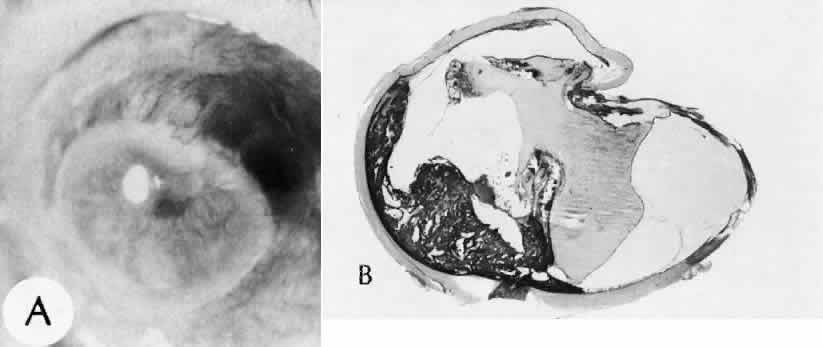

Fig. 42. Two cases of retinal detachment following cataract extraction. A. Retinal detachment was identified 4 weeks after cataract extraction. Fixed retinal folds indicate that the situation is inoperable, so no surgical repair was attempted. The anterior chamber angle has become occluded because of neovascularization associated with ischemic retina. B. Retinal detachment was identified 5 weeks after cataract extraction. Two attempts at surgical repair failed. The large equatorial cystic spaces indicated the presence of a scleral-buckling element. The actual material of the sponge and buckle has been lost during tissue processing. The cystic nature of the detached retinal tissue indicates that there was an extended time between the last retinal reattachment attempt and enucleation. In this case, peripheral anterior synechiae are present. The indication for enucleation was most likely a blind painful eye due to secondary glaucoma and reactive uveitis. (Hematoxylin-eosin stain; × 3.)